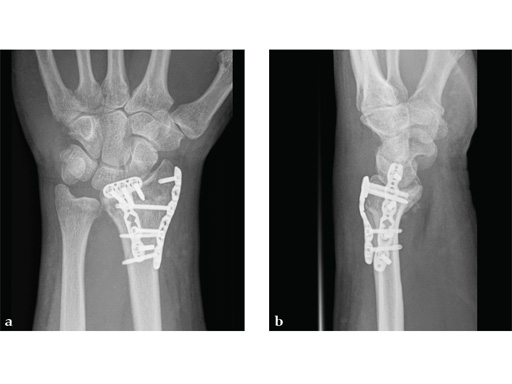

Case 2: A 44-year-old man sustained polytrauma following a car accident. Among his injuries was a distal radial fracture, Mller AO Classification 23-C1.

Case provided by Vitezslav Ruber, Brno, Czech Republic